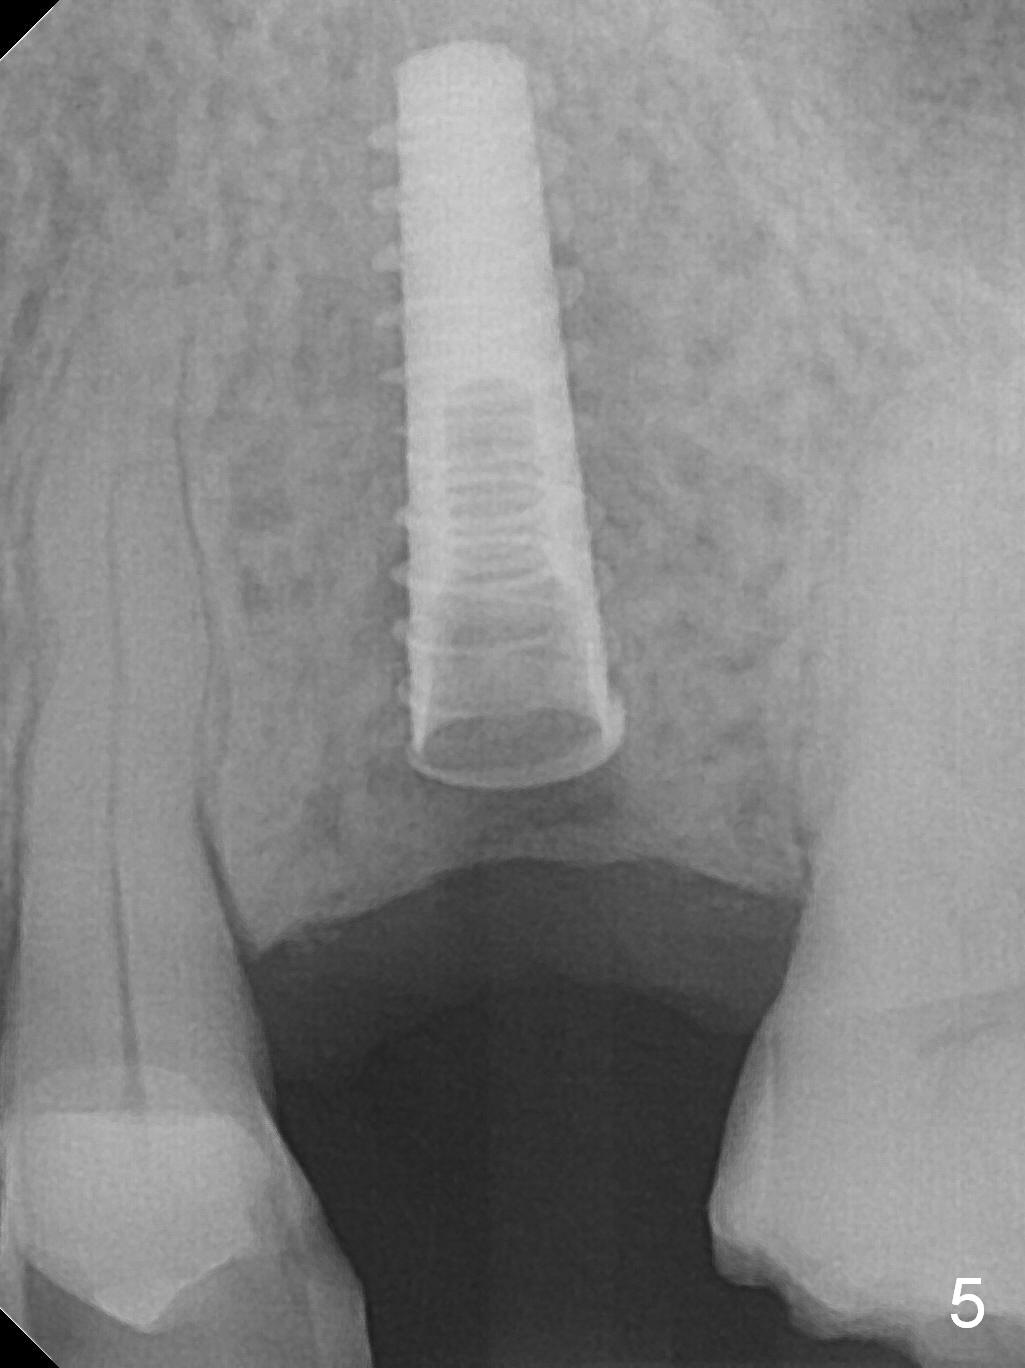

A 74-year-old man has diabetes. Implant osteointegration appears to be slow at #4, while the implant at #28 failed once. He requests implant at #13 (Fig.1). It seems that the bone is wide enough (8 mm, Fig.2 (CT coronal section) (P: palatal)) to hold a 4 mm implant (Fig.3 (axial section)). Since bone density is low at the coronal (100-200 units) and middle (50-100 units) segments (Fig.2), bone condensation will be beneficial. To facilitate wound healing, flapless approach is adopted using 1.6 mm pilot drill (Fig.4), followed by 1.4/2.6 mm bone expander. In fact there is resistance to expansion in the zone 1. Magic expander (3.0 mm) is also tried with difficulty. It appears that bone density is higher than expected. The second portion of Magic Surgical Kit is then used: 3.3 mm Magic Drill for 15 mm (gingival level, followed by Final Drill). A 4x13 mm IBS implant is seated incompletely. The osteotomy is further enlarged by 3.8 mm Magic Drill for 11 mm and deepened with 3 mm drill until 18 mm. Finally the implant is placed at a satisfactory level with insertion torque > 50 Ncm (Fig.5). A 4.5x4(3) mm abutment is placed and periodontal dressing is applied. The patient chooses to return for impression 6 months postop (Fig.6). The abutment changes to a 4x4(4) mm one. The crown is recemented nearly 2 years post cementation, which is related to distal and deep placement of the implant and bruxism (Fig.7).